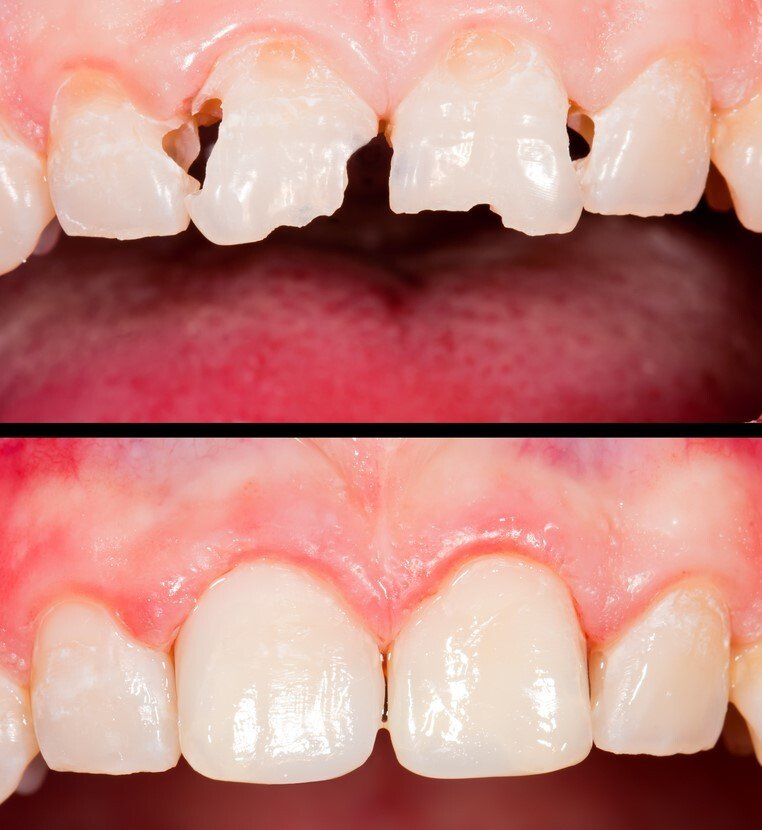

Oral implantology

Implantology is the dental specialty that deals with the replacement of the root of the lost tooth.

The replacement is done through a small surgical procedure to place a piece of titanium inside the jawbone.

The implant has a thread inside where the abutment that will support the prosthetic crown will later be screwed on.

The delay in the replacement of teeth involves functional and anatomical alterations of the buccal dental apparatus, such as: the reabsorption of the maxillary bone, migrations and displacements of remaining teeth or phonetic, aesthetic, masticatory alterations, etc ...

After the evaluation of the implantologist and a very careful diagnosis by the professional team, different solutions are proposed. Depending on the problem posed, which may be: unit loss, multiple loss or complete edentulousness ... the precise technique will be performed in order to improve the quality of life of the patient.

Implantology is one of the medical areas that has evolved the most in recent years. This increases the reliability and comfort of the patient.